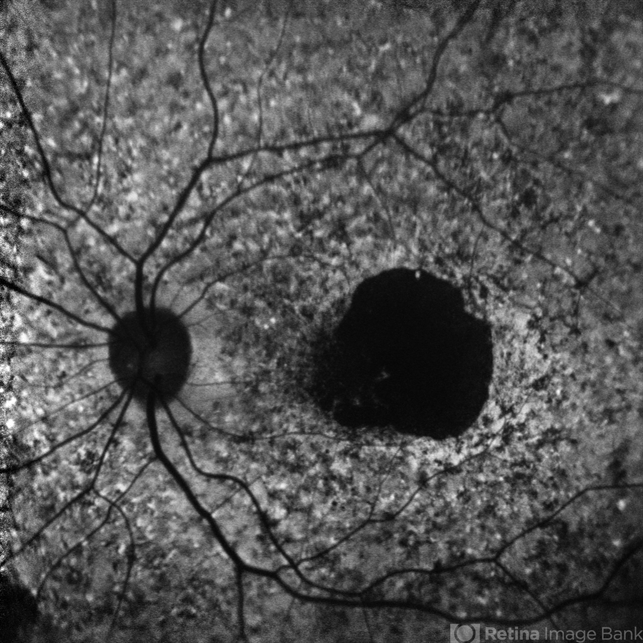

- Fundus autofluorescence image of the left eye of a 39 year old male showing hypoautofluorescence in a case of Stargardt's disease.